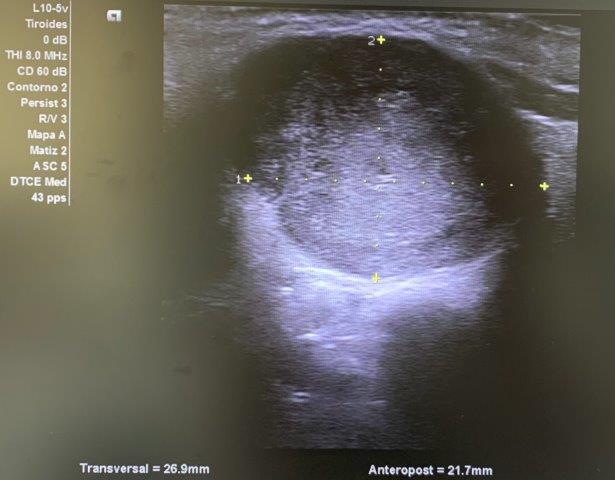

ECO POCUS: imagen isoecoica, heterogénea, redondeada con captación periférica de Doppler, que mide 26.9 x 21.7 mm (corte transversal) y 30.3 mm (corte longitudinal). Vemos un bultoma originado en la cola de glándula parótida.

Ante los hallazgos ecográficos y la persistencia del bultoma, orientamos juicio clínico hacia posible tumoración originada en parótida, con características mixtas de benignidad-malignidad (clínica + ecografía).